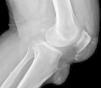

En la exploración física tenía una presión arterial de 160/98mmHg, un índice de masa corporal de 33,5kg/m2 y un perímetro abdominal de 112cm. En rodilla izquierda presentaba un tofo de gran tamaño (fig. 1). Analíticamente destacaba: velocidad de sedimentación globular 65mm, uricemia 10,5mg/dl, triglicéridos 270mg/dl, hemoglobina glucosilada 6,8%, colesterol total normal (colesterol LDL 117mg/dl) y uricosuria 436mg/24 h. El factor reumatoide, los anticuerpos antinucleares y la serología frente a los virus de la hepatitis B, C e inmunodeficiencia humana, Brucella, Borrelia burgdorferi y Parvovirus B19 fueron normales o negativas. Radiológicamente se observaba, en la rodilla izquierda, un notable aumento de partes blandas con masas pre e infrarrotulianas con calcio, en relación con tofos calcificados. La rodilla derecha también presentaba datos de artropatía con calcificaciones capsulares y erosión ósea en borde lateral del cóndilo femoral e incipiente condrocalcinosis (fig. 2). Con el diagnóstico de brote poliarticular agudo gotoso en paciente con gota tofácea crónica, se prescribieron medidas higiénico-dietéticas, indometacina (50mg/8 h), enalapril 10mg/día y atorvastatina 10mg/día. Con ello, el paciente quedó asintomático. A los 21 días, se inició tratamiento con colquicina 0,5mg/día y 100mg/día de alopurinol, sin que haya presentado nuevos brotes agudos. Seis meses después, con 300mg/día de alopurinol y colquicina, el paciente está asintomático, su uricemia es de 5,4mg/dl y han disminuido de tamaño los tofos.